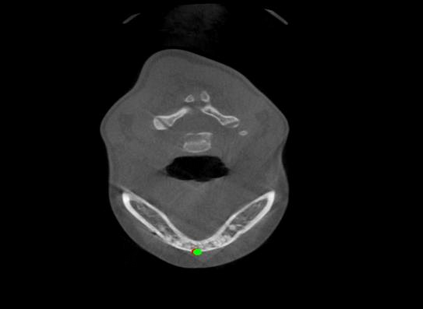

Detecting 3D landmarks on cone-beam computed tomography (CBCT) is crucial to assessing and quantifying the anatomical abnormalities in 3D cephalometric analysis. However, the current methods are time-consuming and suffer from large biases in landmark localization, leading to unreliable diagnosis results. In this work, we propose a novel Structure-Aware Long Short-Term Memory framework (SA-LSTM) for efficient and accurate 3D landmark detection. To reduce the computational burden, SA-LSTM is designed in two stages. It first locates the coarse landmarks via heatmap regression on a down-sampled CBCT volume and then progressively refines landmarks by attentive offset regression using multi-resolution cropped patches. To boost accuracy, SA-LSTM captures global-local dependence among the cropping patches via self-attention. Specifically, a novel graph attention module implicitly encodes the landmark's global structure to rationalize the predicted position. Moreover, a novel attention-gated module recursively filters irrelevant local features and maintains high-confident local predictions for aggregating the final result. Experiments conducted on an in-house dataset and a public dataset show that our method outperforms state-of-the-art methods, achieving 1.64 mm and 2.37 mm average errors, respectively. Furthermore, our method is very efficient, taking only 0.5 seconds for inferring the whole CBCT volume of resolution 768$\times$768$\times$576.